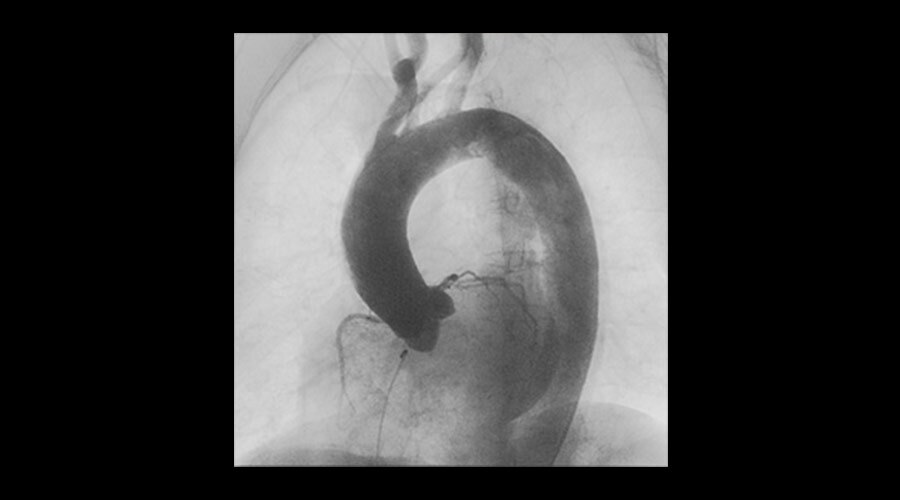

Klinik Görüntüler

-

Aortic procedure